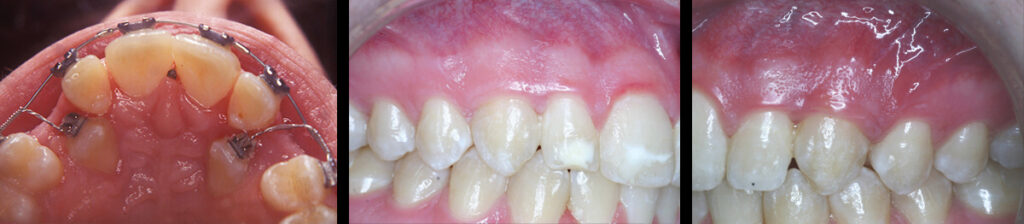

Impacted Teeth:

As children grow, the erupting permanent teeth push out the overlying baby tooth. When permanent teeth fail to come in, they are termed …impacted. This occurs with upper canines as well as other teeth. In these situations, a periodontist may be asked to surgically expose the tooth and attach a chain so that an orthodontist can actively

engage the tooth, assisting it in a successful erupt.